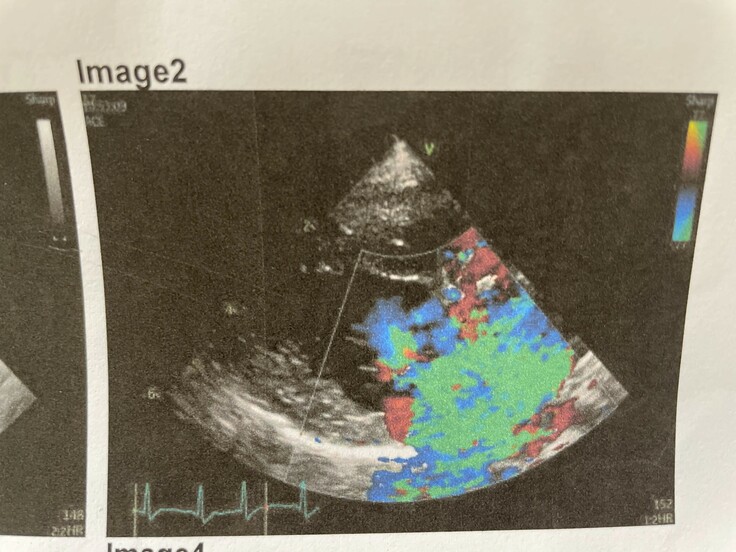

(こちらは心臓の写真です。写真のカラー部分が逆流した血液になります。)

心臓病のステージはA~Dまであり、ミルクはそのうちのB2(Cに近い)と診断されました。

今は薬で肺水腫を防げているギリギリの状態であり、肺水腫になると余命は9ヶ月。